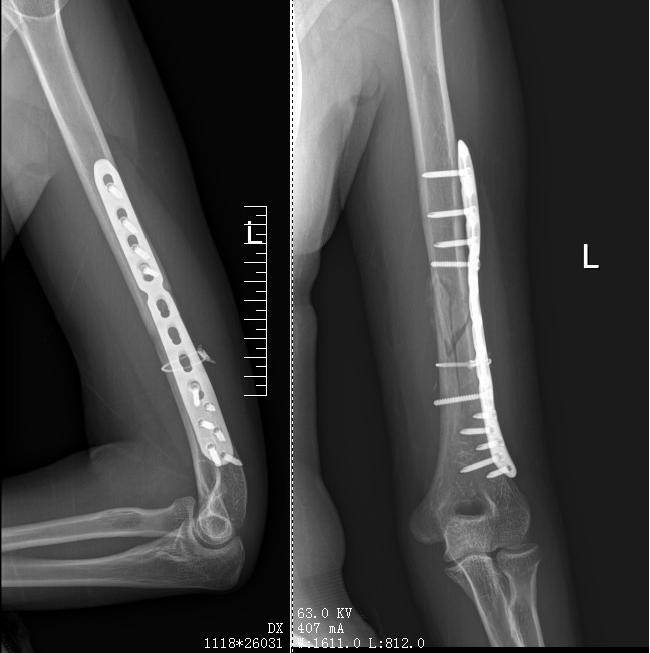

近期,一款备受欢迎的竞技游戏——掰手腕,却给参赛者带来了意外的伤害。27岁的韩女士在陪同朋友参加女子组比赛时,仅用不到半分钟的时间,由于用力过猛,不幸导致上臂肱骨螺旋状骨折。术后,韩女士身上留下了约30厘米的显著疤痕,康复过程异常艰难。29岁的张女士,在单位举办的拔河比赛中获胜后,不幸遭遇骨折。经核实,患者左侧肱骨中下段区域存在骨折情况。同时,左侧上臂的桡神经亦遭受损伤。16岁少年小陈在课间休息期间,参与类似活动时不幸遭遇骨折。

郑州市骨科医院的研究表明,每年有超过十位患者,包括张女士和小陈,因参与拔河活动导致骨折。骨折多发生在肱骨中下段。这一数据警示公众,拔河运动可能存在安全隐患,应引起重视。

竞技扳手腕赛事中存在潜在安全风险。操作不当可能导致伤害。患者可能遭受腕、肘、肩关节的韧带及肌肉损伤,影响日常生活。在极端案例中,如韩女士、张女士所遭遇,可能出现肱骨中下段骨折,并伴随神经损伤。此类患者须承受漫长的痛苦恢复过程,且有可能遭受后遗症困扰,进而对他们的身体机能造成影响。